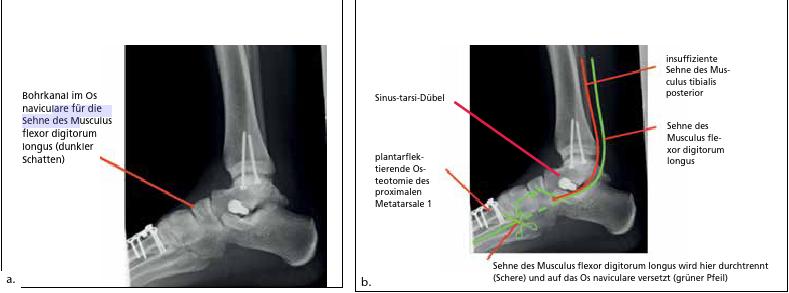

- In sehr vielen Fällen wird auf die degenerativ aufgefaserte Sehne des Musculus tibialis posterior eine gesunde Nachbarsehne „huckepack“ verpflanzt, um die ungenügend funktionierende Sehne des Musculus tibialis posterior in ihrer Funktion zu unterstützen. Hierfür wird in aller Regel die Sehne des Musculus flexor digitorum longus, die genau neben der Sehne des Musculus tibialis posterior verläuft, proximal des „Master Knot of Henry“ (Kreuzung mit der Sehne des Musculus flexor hallucis longus im Bereich der Fußsohle) abgetrennt und auf das Os naviculare oder/und das Os cuneiforme mediale zum Beispiel transossär verpflanzt. Die Funktionseinschränkung durch Absetzen der Sehne des Musculus flexor digitorum longus ist minimal und für den Patienten oft nicht merklich, da faserige Verbindungen mit der Sehne des Musculus flexor hallucis longus bestehen und diese Sehne dann die Funktion der abgetrennten Sehne teilweise übernimmt. Auch gibt es noch die kurzen, in der Fußsohle angesiedelten Zehenbeugermuskeln, die diesen „Verlust“ ausreichend kompensieren.

- Die Abkippung des Talocalcaneargelenks, die zum Rückfußvalgus führt, wird mittels medialisierender Calcaneusosteotomie oder eines Sinustarsi-Dübels korrigiert. Ein Sinus-tarsi-Dübel ist nicht nur Kindern und Jugendlichen vorbehalten.

- Schließlich muss der 1. Strahl adressiert werden, der häufig nach Korrektur des Rückfußes angehoben (dorsalextendiert) steht. Wenn der 1. Strahl nicht bewusst plantarisiert wird, fehlt dem Fuß ein großer Anteil seiner intrinsischen Stabilität, die der 1. Strahl den pronatorischen Momenten des Rückfußes entgegenwirken lässt. Die Plantarisierung des 1. Strahls gelingt durch eine plantarflektierende Osteotomie des proximalen Metatarsale 1 oder des Os cuneiforme mediale (Abb. 15).